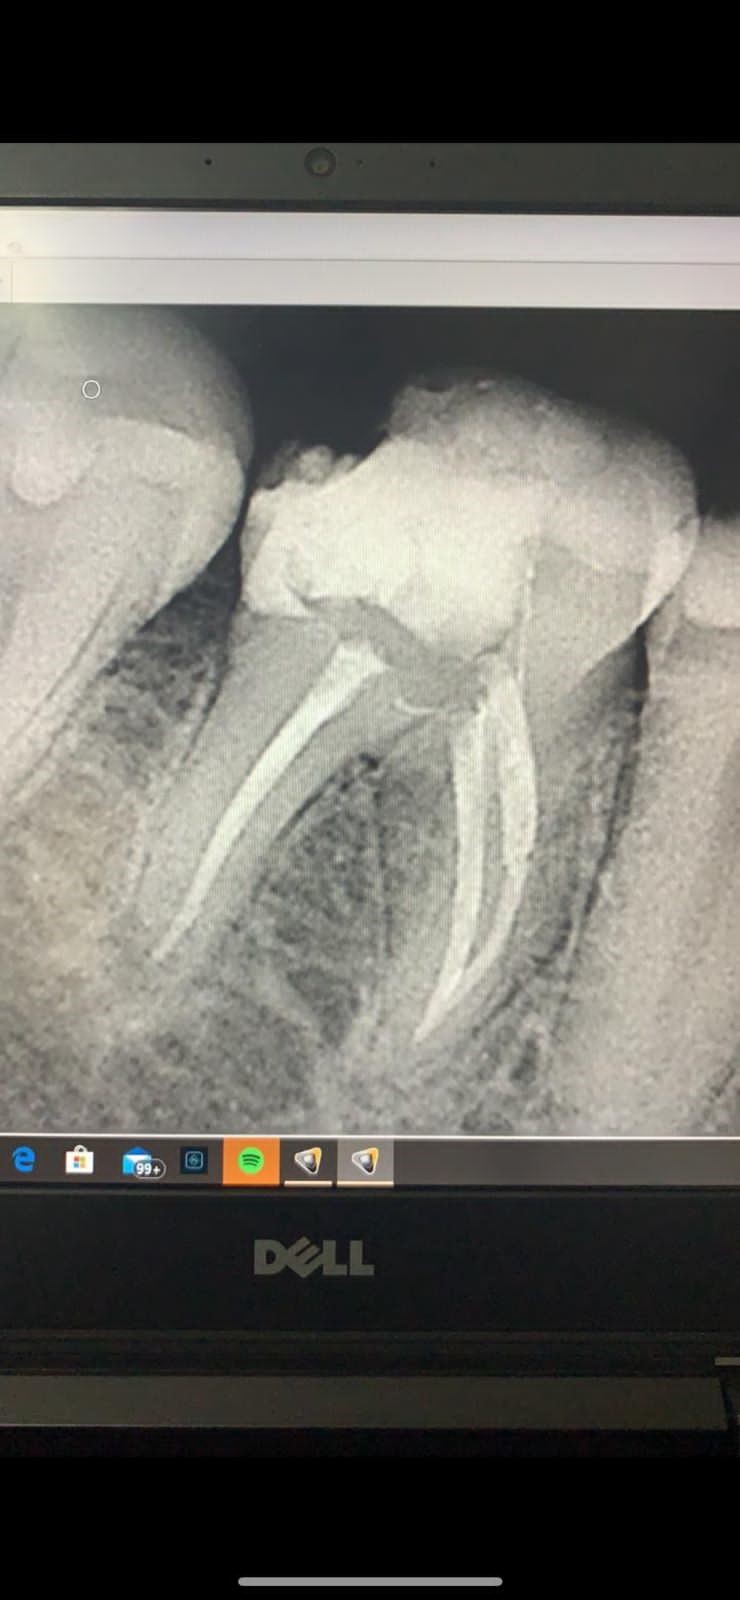

Galeria de Imagenes

Avances en procedicmiento de Endodoncia